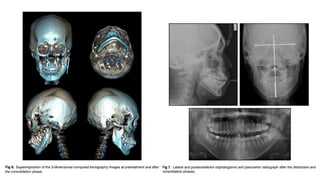

• Three-dimensional computed tomography

images showed deficiencies of the left

condylar and coronoid processes, along

with ramus hypoplasia and chin deviation.

• Superimposition of 3-dimensional computed tomographs showed that after distraction osteogenesis

and the consolidation phase, the shorter ramus was lengthened to 54.5 mm, the mandible was

advanced compared with pretreatment, and the ANB angle decreased to 2.3.

• However, the overall superimposition showed that some relapse occurred during orthodontic